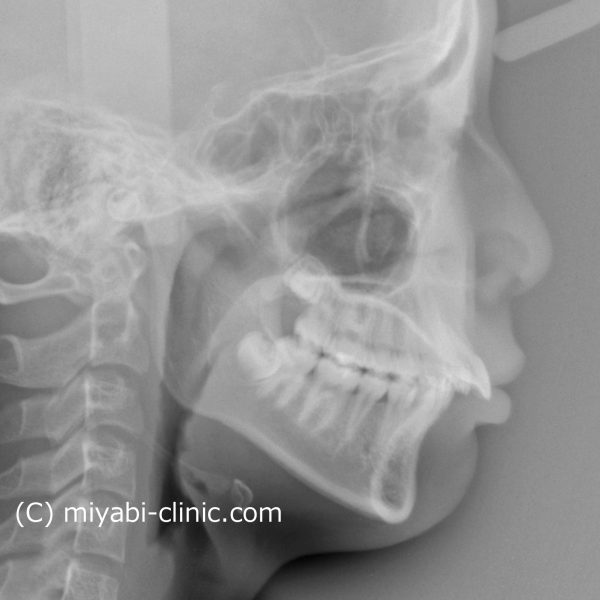

レントゲン写真を 見てみましょう

前歯は 強く傾斜していて、くちびるを押し出しいることが分かります

治療前後で前歯の傾斜がかなり改善しました。

レントゲン写真で確認しても上下の前歯は 大きく下がり、

前に飛び出していた上下の前歯の傾きが正常化しました。